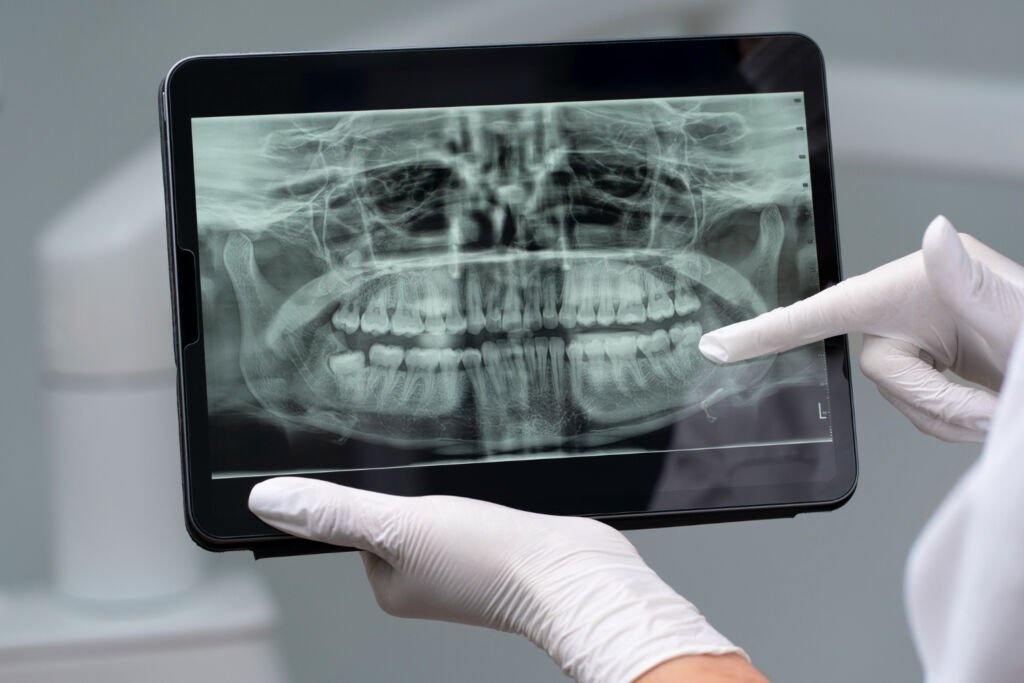

Imágenes diagnósticas que generan confianza y precisión

En TAC Facial somos especialistas en imágenes 2D y 3D para odontología, cirugía maxilofacial y evaluación facial. Brindamos claridad diagnóstica en cada estudio, asegurando que profesionales y pacientes cuenten con información precisa para planificar tratamientos con seguridad.

Nuestra tecnología Cone Beam 3D permite visualizar estructuras óseas y dentales con alta definición, favoreciendo diagnósticos exactos y resultados clínicos confiables.